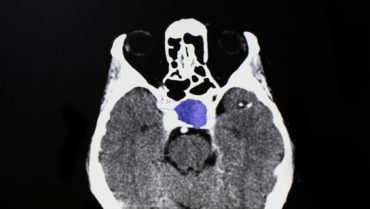

MRI with and without contrast of the brain and/or orbits with attention to the sella is the recommended medium for diagnosis (Figure 2). A patient with a confirmed pituitary macroadenoma should be referred to both neurosurgery and endocrinology. Asymptomatic patients with incidental macroadenomas should receive continued ophthalmologic surveillance because any new visual symptoms strongly indicate a need for surgical intervention. Although there are no established guidelines for the length of ophthalmologic follow-up, lesion size and a progression of visual field defects should inform decisions regarding timeline.

Figure 2. Sagittal midline precontrast T1-weighted MRI showing enlargement of the sella turcica and superior extension of a pituitary macroadenoma (arrow, A). Coronal T1-weighted MRI with contrast showing the optic chiasm stretched and compressed over the mass (arrows, B).